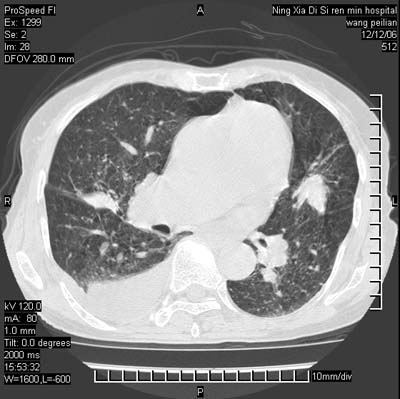

两肺可见多个大小不等的结节,左侧有胸水,纵隔淋巴结增大,考虑是细支气管肺泡癌

两肺尖纤维索状影,两下肺结节块状影,且有钙化灶,右胸腔积液。考虑肺结核并胸膜炎。

双侧肺结核伴右侧胸腔积液.

两肺尖纤维索状影,两下肺结节块状影,且有钙化灶,右胸腔积液。考虑肺结核并胸膜炎肺间质纤维化

两肺以间质性病变为主,并有胸腔积液,考虑结核

考虑:1、慢性支气管炎合并全小叶型肺气肿、间质纤维化;

2、双肺结核;

3、右侧胸膜炎(积液)。

1、双肺继发型肺结核(以纤维、增殖灶为主);

2、右侧胸腔积液;

3、其余符合老年肺改变。

双肺见多个结节状及条索状影,双侧胸腔积液,右侧叶间积液,考虑结核性胸膜炎